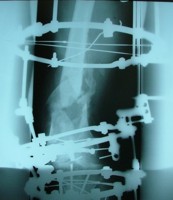

تهیه و تامین تجهیزات ارتوپدی و مشارکت در انجام اعمال جراحی ارتوپدی و عمل‌های نادر عضو تیم جراحی افزایش قد -جهت ترمیم شکستگی های قدیمی و جوش نخورده گی ها -طویل کردن اندامها- طویل کردن انگشت قطع شده - تعویض مفصل لگن _تعویض مفصل زانو _ بازسازی رباطACLوPCL_اصلاح ناهنجاریهای مادر زادی -با همکاری پزشکان و متخصصان مجرب آموزش دیده در روسیه و اتریش و سوئیس بروش جراحی ایلیزاروف و lon و lsa و واگنر و اسلایدینگ نیز جدید ترین روش افزایش قد و اندام در سال 1397 بنام hil هیل برای اولین بار- افزایش قد به 6 روش جراحی و جدیدترین روش در اروپا و روسیه. آدرس مطب _تهرانسر بلوار اصلی مجتمع سهند طبقه4 واحد 410

قطعات الیزاروف:

الیزاروف دارای عناصر اولیه و عناصر ثانویه است:

Bolt slotted-pin-ringعناصر اولی:

ها را به هم وصل می کند. .ringعناصر ثانویه: تمام قطعاتی که

پین ها باید در دو طرف رینگ گذاشته شود تا رینگ تاب نخورد،واشر کونیکال یا اسفریکال واشر تا 5/7(نیست به رینگ) درجه زاویه به راد می دهد .

تهیه و تامین تجهیزات  ومشارکت در انجام اعمال جراحی  ارتوپدی

-جهت ترمیم شکستگی های قدیمی و جوش نخورده گی ها -

طویل کردن اندامها- طویل کردن انگشت

-اصلاح ناهنجاریهای مادر زادی

باهمکاری پزشکان و متخصصان مجرب بروش جراحی ایلیزاروف